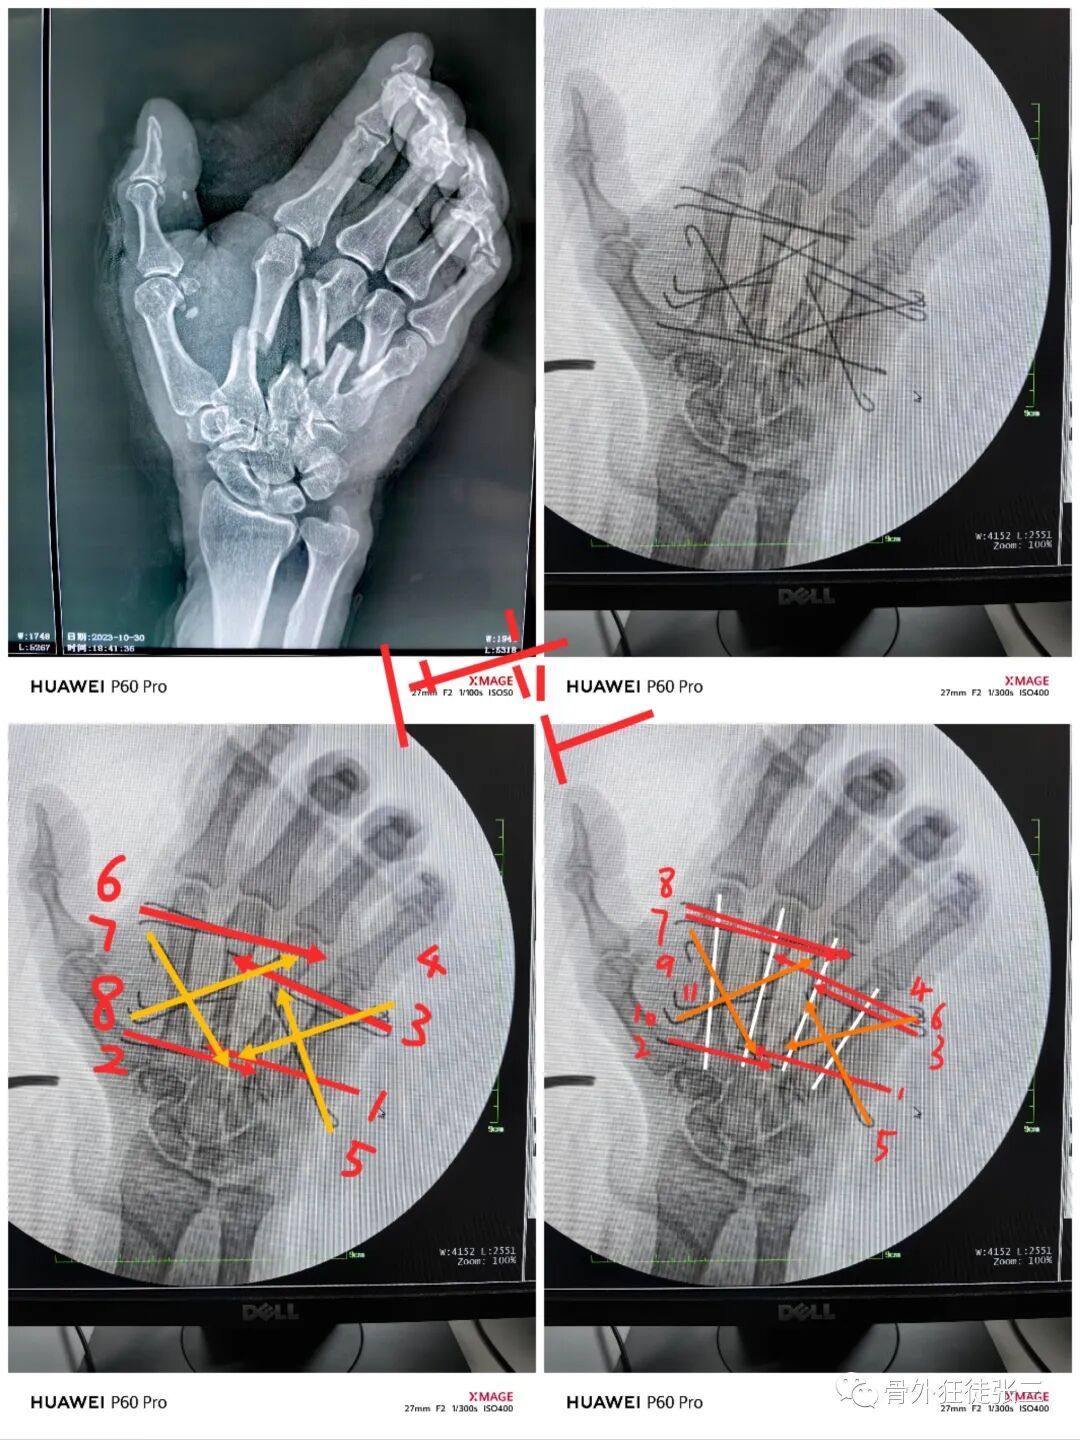

病例6,开放性第2345掌骨骨折,克氏针支架

病例23,严重复杂手外伤,多发骨折,克氏针固定

病例32,第345掌骨开放性骨折,克氏针髓内+克氏针支架